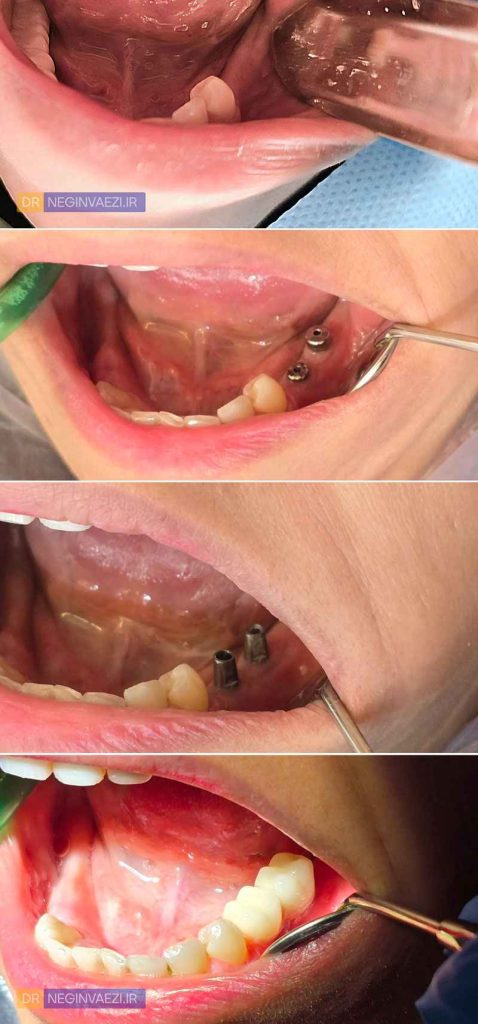

2- عکس قبل و بعد ایمپلنت دندان فک پایین

در اینجا نیز می توانید عکس های بخشی از مراحل کاشت ایمپلنت را مشاهده کنید. مرحله مربوط به بخش جراحی، بدلیل صحنه های حاوی خون و جراحات، درج نمی شود.

کاشت پایه ایمپلنت (فیکسچر) و سپس آنکاور آن

تحت شرایط بی حسی کامل و بدون درد، لثه بیمار کنار زده شده و پس از آماده سازی استخوان، پایه ایمپلنت در محل مناسب قرار داده شده است. پس از طی شدن زمان مناسب و رسیدن به استئواینتگربشن (جوش خوردن پایه ایمپلنت با استخوان فک)، روی پایه ها باز شده و healing abutment با هدف فرم دهی مناسب لثه ها قرار داده میشود.

قالبگیری و نصب اباتمنت

سپس قالبگیری به روش مناسب انجام شده و abutment های اصلی بر روی ایمپلنت ها نصب گردیدند.

امتحان و تحویل روکش های نهایی

پس از جلسه ی امتحان روکش ها و انجام اصلاحات جزئی (در صورت نیاز)، روکش ها نصب و تحویل داده شدند.

ایمپلنت های سمت مقابل فک پایین این بیمار نیز در مراحل کاشت می باشد که پس از تکمیل ، تصاویر آن اضافه خواهد شد. اما در حد همین دو ایمپلنت فک پایین نیز می تواند نتیجه واقعی و قابل توجهی رو مشاهده کرد. به تصویر نهایی زیر توجه نمایید.